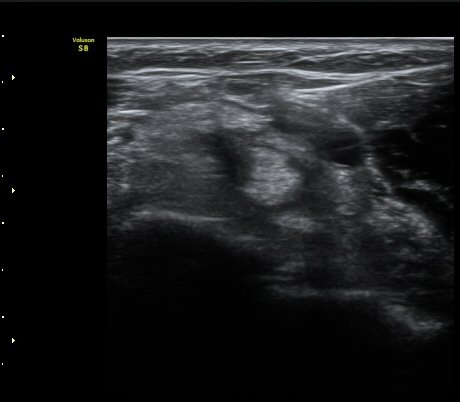

ÆÈ²ÞÄ¡ ¾Õ Ⱦ´Ü¸é°Ë»ç¿¡¼­ À̵ιڱÙÀÌ ÈûÁÙ·Î ÀÌÇàµÇ´Â °ÍÀÌ °üÂûµÈ´Ù(±×¸² 1, 2).

ŽÃËÀÚ¸¦ Á¶±Ý ¸»´ÜÀ¸·Î À̵¿ÇÏ´Ï À̵ιڱ٠ÈûÁÙÀÌ ¶Ñ·ÈÇÏ°Ô °üÂûµÇ°í ÇÔÁÙ ÁÖÀ§¿¡